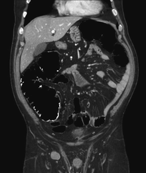

Synchronous contralateral adrenal metastasis of colorectal cancer: case report

Micaela Raices and others

Journal of Surgical Case Reports, Volume 2017, Issue 6, June 2017, rjx098, https://doi.org/10.1093/jscr/rjx098